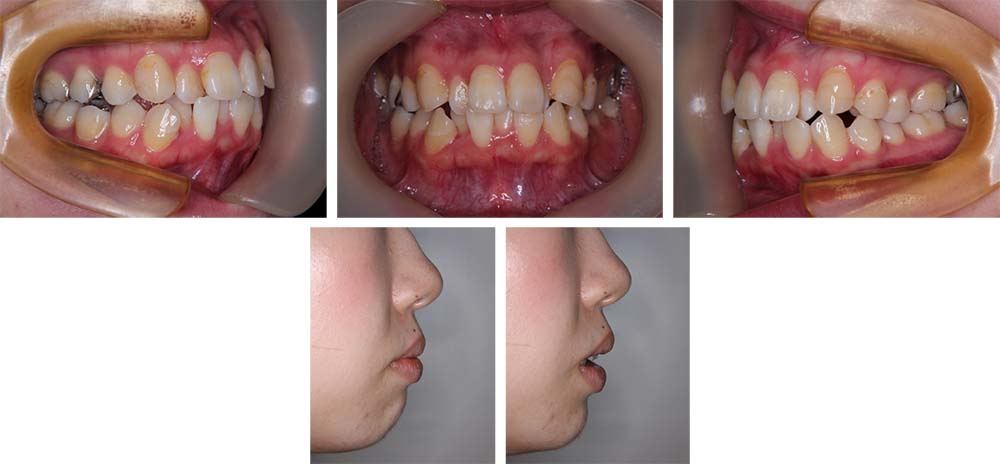

治療前

治療後

上顎前歯の前突と下顎前歯部叢生、口元の突出とガミースマイルを主訴にご来院いただいた。上顎前歯は歯槽部から前傾して、下顎前歯は右側側切歯が舌側転位していて、上顎同様全体的に前突していた。側貌セファログラムの分析や模型分析などから下顎前歯部叢生を伴う上下顎前突と診断した。ガミースマイルの改善については歯科矯正治療での限界について十分に説明のうえ、治療の目標の一つとしてガミースマイルの「軽減」を挙げた。患者さんの希望で上下顎舌側マルチブラケット装置を使用することとして、上下顎小臼歯を抜歯していただき矯正用アンカースクリューを併用して動的治療を行った。上下顎前歯の後退が十分に行われ、口元の安寧が得られた。ガミースマイルについては診断時に説明していた通り、スマイル時に歯肉の露出が全くない状態とすることはできなかったが、軽減することはできた。動的治療期間3年10か月間、調整来院34回。